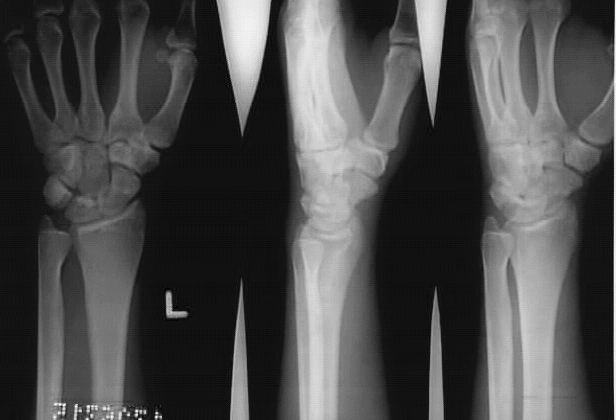

Upper Limbs:Wrist Fracture 3 Views: